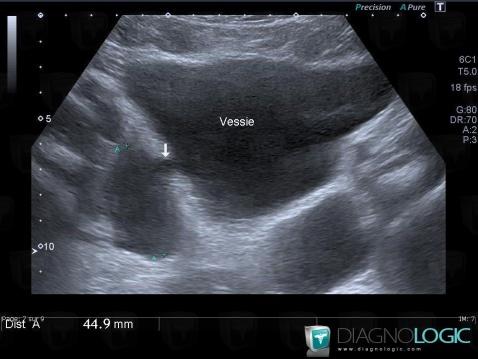

Diverticule-vessie, Vessie, Pelvis / Périnée, Echographie

- Diagnostic Diverticule de vessie, Localisation(s) Pelvis / Périnée, comportant les gammes Masse pelvienne kystiqueVessie, comportant les gammes Masse de la paroi vesicale